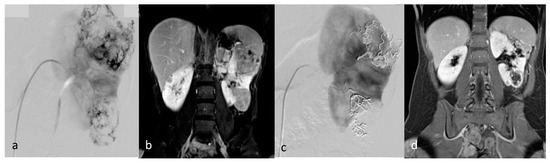

Figure 1.

A 70-year-old patient with right AML (*), Wunderlich Syndrome and aneurysm (white arrow). (a) Yellow ROI showing retroperitoneal hemorrhage (65 UH) on axial computed tomography without injection; (b) Axial computed tomography with injection and arterial acquisition; (c) Coronal computed tomography with injection and arterial acquisition.